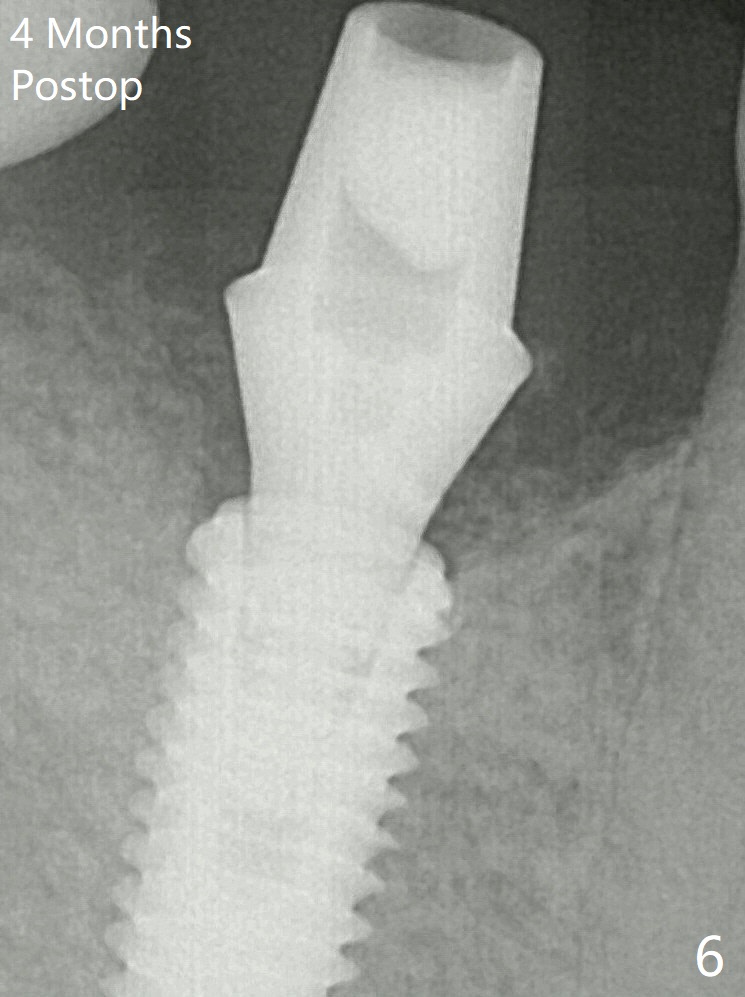

After insertion of a 5.7x5.5(3) mm abutment, Vanilla Graft is placed (Fig.5 * with 2 mm buccal gap). The abutment with a provisional is loose 4 months postop (Fig.6). The abutment screw is loose and fractured 8 and 11 months post cementation, respectively (Fig.7). The fractured screw seems to be loose within the implant well and is easily re-winded out.